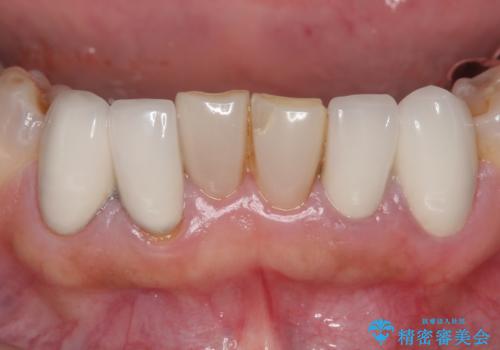

- 上下顎前歯部の見た目が気になるといらっしゃった方の症例です。

上顎は左4番から右4番までの8歯、下顎は左3番から右3番までの6歯、計14歯をオールセラミッククラウンにより補綴しました。